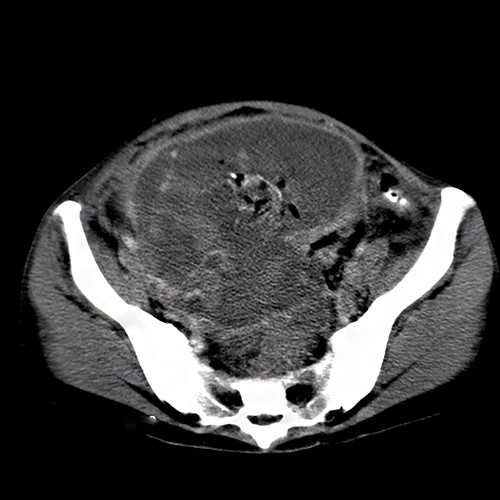

Six weeks later, she reported that she had been feeling of heaviness in her abdomen and lately developed abdominal pain that has been increasing in intensity. She was referred to our hospital for further investigations. Physical examination showed a soft and mildly tender abdomen. Lab tests revealed a negative pregnancy test, a normal clotting profile, and mild anemia. Ultrasonography (US) revealed normal adnexa, an empty uterus and a heterogenic abdominal mass anterior to the uterus. The fetal crown lump length diameter was measured and corresponded to ~9 weeks of gestation. Computed tomography (CT) scan revealed a heterogenic mass outside the uterus measuring 11 × 8 cm (Fig. 1) and raised the possibility of abdominal pregnancy. Under general anesthesia, laparotomy exposed a gestational sac implanted outside the uterus on the anterior abdominal wall. Blood clots and pieces of placental tissue were also noticed. The gestational sac was incised, and an unviable fetus was found (Fig. 2). The patient received two blood units during the operation. The patient had an uneventful course of recovery and was discharged after 6 days.

A heterogenic mass outside the uterus measuring 11 × 8 cm and containing blood clots and placental tissues.